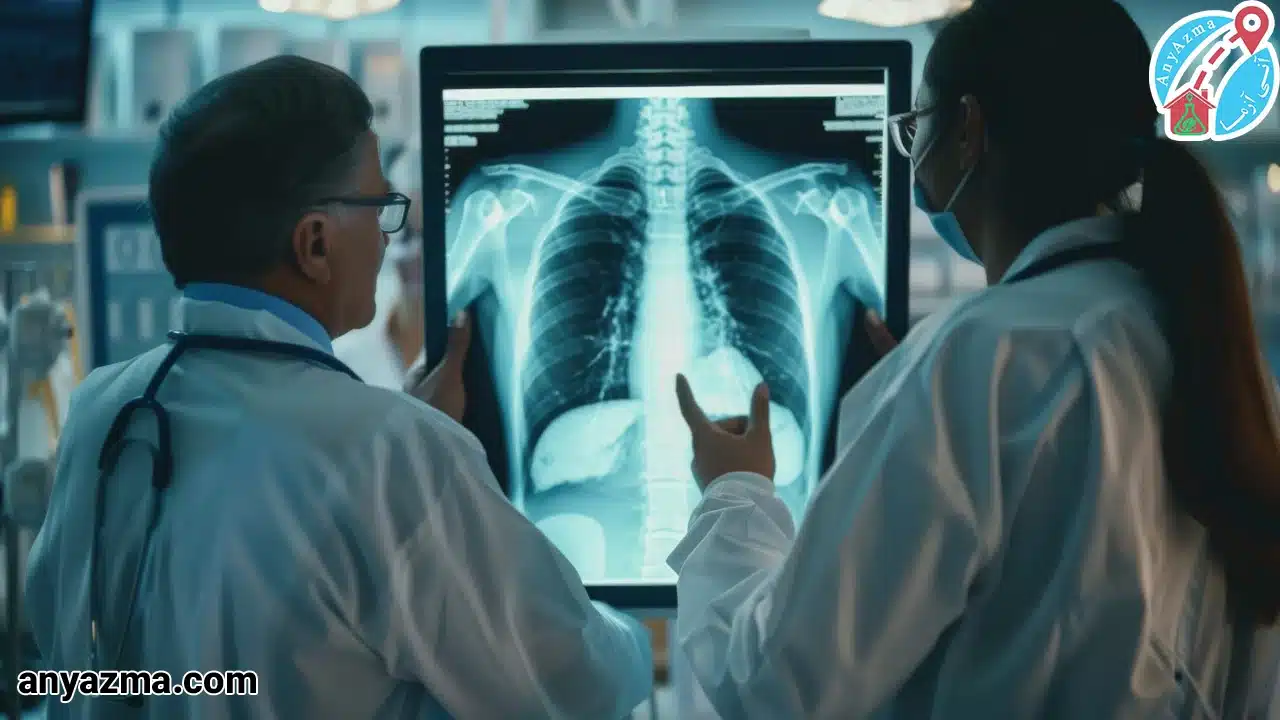

خدمات رادیولوژی ستون فقرات در منزل توسط آنی آزما، برای بیمارانی است که به وجود درد شدید، آسیبهای نخاعی، یا ناتوانی حرکتی، نمیتوانند برای تصویربرداری به مراکز درمانی مراجعه کنند. ستون فقرات، محور اصلی بدن ما است و تشخیص دقیق مشکلات آن نیازمند حفظ کمترین حرکت در بیمار است.

ما با بهرهگیری از دستگاههای رادیولوژی در منزل (دستگاههای قابل حمل) و کادر فنی باتجربه، تصویربرداری تخصصی از نواحی مختلف ستون فقرات (مانند گردنی، سینهای و کمری) را با همان استاندارد و دقت مراکز رادیولوژی، مستقیما در محل اقامت شما ارائه میدهیم.

ما با بهرهگیری از دستگاههای رادیولوژی در منزل (دستگاههای قابل حمل) و کادر فنی باتجربه، تصویربرداری تخصصی از نواحی مختلف ستون فقرات (مانند گردنی، سینهای و کمری) را با همان استاندارد و دقت مراکز رادیولوژی، مستقیما در محل اقامت شما ارائه میدهیم.